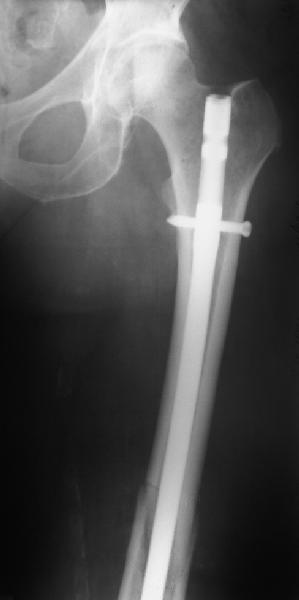

В приложении - недавний перипротезный перелом.

Хотя закрытый остеосинтез блокированным гвоздем выглядит технически проще, особенно при диафизарных переломах. Не говоря о биомеханических преимуществах внутрикостного имплантата, еще меньшей инвазивности, возможности динамизации при проблемах со сращением... Стоимость гвоздей и пластин сопоставимая, на рынке есть масса отечественных предложений.